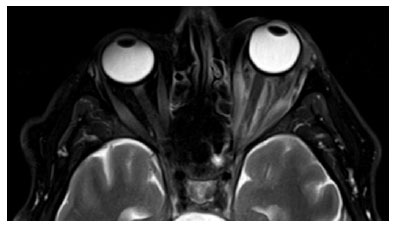

At five days, the patient agreed to undergo magnetic resonance imaging and venography (MRV), which revealed thromboses in the bilateral cavernous sinus (worse in the left eye), left superior ophthalmic vein, and right inferolateral orbital vein (Figures 1 and 2), for which heparin therapy was initiated. Blood cultures revealed methicillin-resistant Staphylococcus aureus. Therefore, cefepime was switched to ceftaroline for enhanced central nervous system penetration.

02-fig02.jpg)